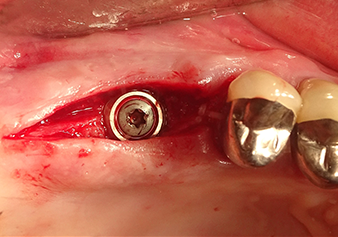

Implantation and prosthetic restoration

To move the augmentation material in the direction of the maxillary sinus atraumatically, the implant was inserted very slowly by hand (Fig. 9). In the process, the membrane was pushed in the cranial direction once again. After two months, the surgical site healed without irritation. Six months later, the x-ray check showed a significant increase in opacity as an indication of ossification (Fig. 10). The prosthetic restoration was carried out with a metal-ceramic crown.

In the author’s practice, the membrane is routinely lifted in two phases. Alternatively, the method specified by the manufacturer is also suitable. In this case, the implant bed is first prepared and only then is the bony sinus floor opened on a small scale with the Z35P instrument. As a result of the very atraumatic method, the patient experienced no postoperative pain and was able to return to work the following day. In the author’s practice, this is true of 90% of patients.